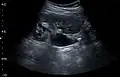

Renal ultrasonography can sometimes be useful, because it gives details about the presence of hydronephrosis, suggesting that the stone is blocking the outflow of urine.[58] Radiolucent stones, which do not appear on KUB, may show up on ultrasound imaging studies. Other advantages of renal ultrasonography include its low cost and absence of radiation exposure. Ultrasound imaging is useful for detecting stones in situations where X-rays or CT scans are discouraged, such as in children or pregnant women.[66] Despite these advantages, renal ultrasonography in 2009 was not considered a substitute for noncontrast helical CT scan in the initial diagnostic evaluation of urolithiasis.[65] The main reason for this is that, compared with CT, renal ultrasonography more often fails to detect small stones (especially ureteral stones) and other serious disorders that could be causing the symptoms.[14]

On the contrary, a 2014 study suggested that ultrasonography should be used as the initial diagnostic imaging test, with further imaging studies be performed at the discretion of the physician on the basis of clinical judgment, and using ultrasonography rather than CT as an initial diagnostic test results in less radiation exposure and equally good outcome.[67]

Renal ultrasonograph of a stone located at the pyeloureteric junction with accompanying hydronephrosis.